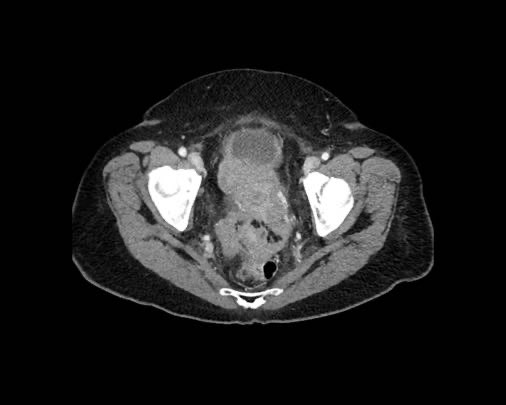

Cuộn xem ảnh CT

Ca lâm sàng 1

Cuộn qua các lát cắt.

Bạn có thể phát hiện tất cả các tổn thương cấy ghép phúc mạc không?

Bệnh nhân này đã được phẫu thuật và toàn bộ phúc mạc được ghi nhận phủ kín bởi các tổn thương u dạng kê.